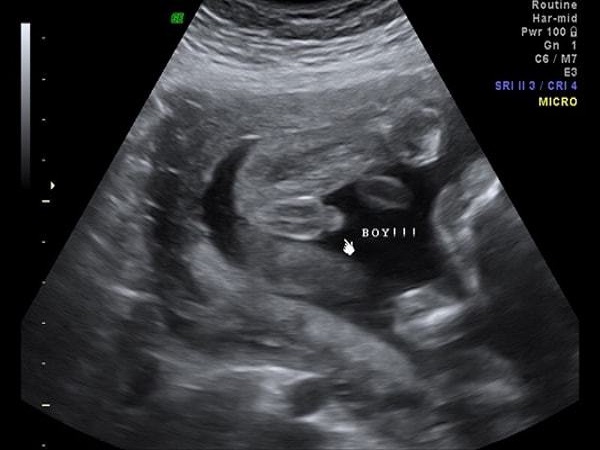

男孩B超腿部间图片

1、男孩:一般来说,B超图片是能够看清楚胎儿腿部间的特征的,如果B超单上胎儿的腿部间出现凸起的东西,或者是有圆圆的和尖尖的亮点的话,那就是男性的外生殖器官,说明怀的就是男宝宝。